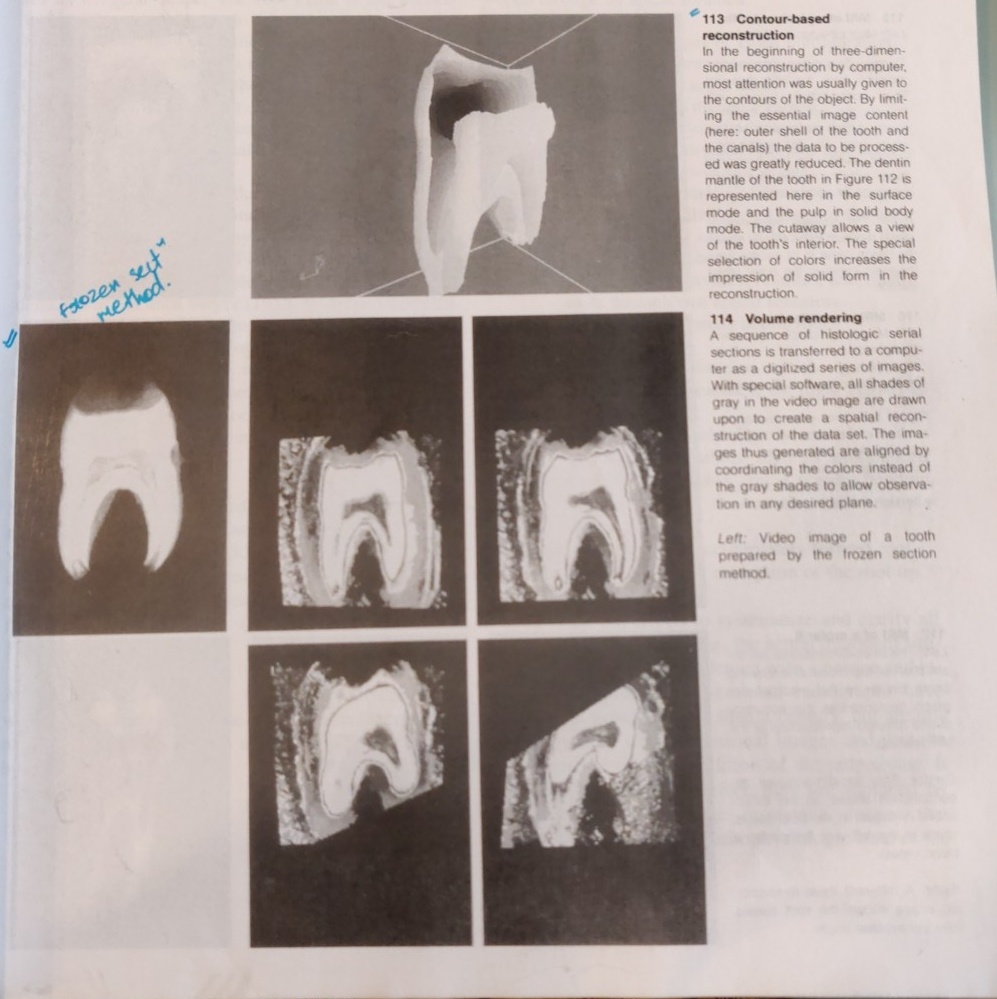

From a historical perspective we see a long tradition of striving to better describe the anatomy of the teeth. Preparations of 20 micrometer thick frozen sections were continuously recorded on videotape, producing data to serve as the basis for computerized three-dimensional reconstructions. In a contour-based reconstruction only the surface outlines of the tooth and the canals are used for input (Baumann et al. 1993d, 1994b). From this emerges a contour line, surface, or solid body model that can be viewed from any desired angle.

Faster computers permit the use of all shades of gray in a video image to create a volume-based reconstruction (volume rendering). Through ray-tracing, isotropic voxels (points in space) are created in which the raw unaltered data is drawn upon for three-dimensional reconstruction (Baumann 195, Baumann et al. 1993d).

Images are created that can be viewed, sectioned, colored, zoomed, or rotated in any desired plane. This makes possible views into the endodontic space that were prevoiusly unknown.